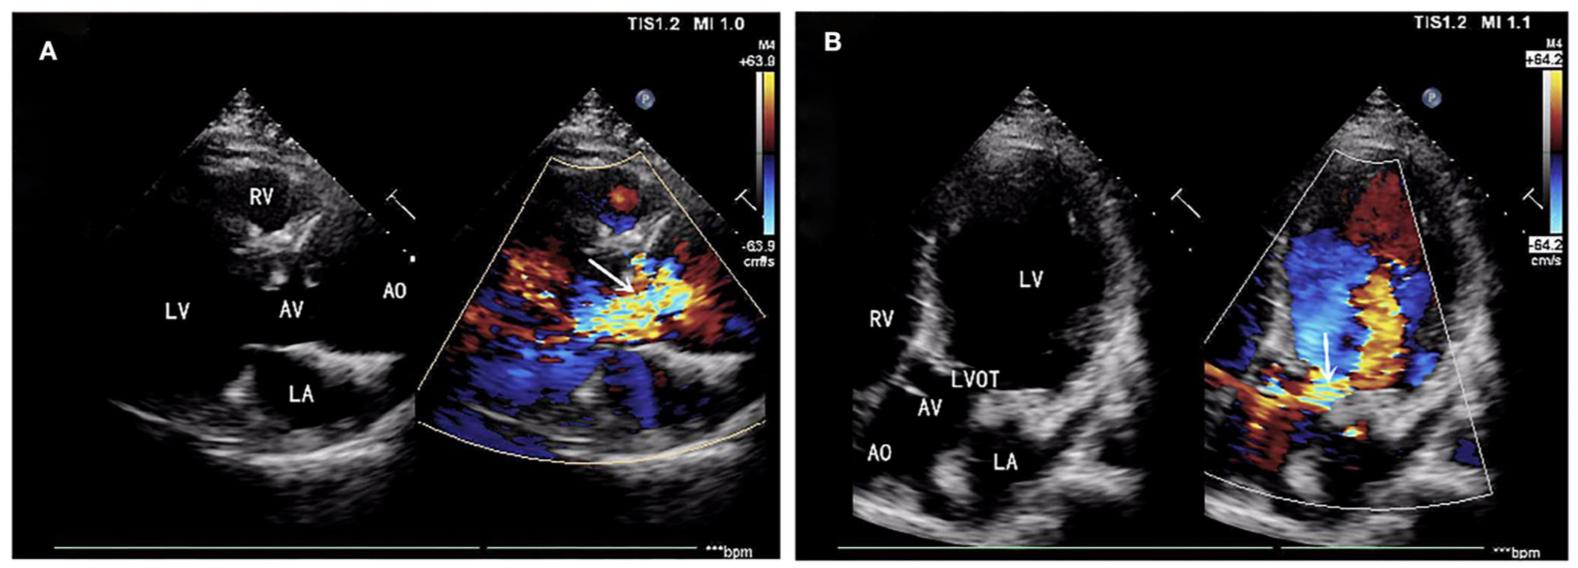

一名39岁男性患者因持续咯血3周而入院。患者是典型的TOF,而不是SD I型TOF。此前,他接受了法洛四联症根治性手术,包括缓解右心室流出道梗阻,并在21岁时修复室间隔缺损。在胸骨左侧第二肋间间隙发现舒张期杂音,其他体检结果均为阴性。根据心脏超声心动图观察到的结果,诊断为窦管连接部和升主动脉扩张(环,3.17厘米;窦,最大5.82厘米;近端升主动脉,4.14厘米)和主动脉瓣关闭不全合并严重AR(图1A)。术前胸部CT扫描显示主动脉根部直径为55.19 mm×67.09 mm(图2)。同时,还检测到LVOT的局部阻塞(图1B),LVOT阻塞的梯度为23 mmHg。经临床评估,该患者接受了包括David I plus修复主动脉瓣手术和同时重建左心室流出道的手术。

图1.(A)主动脉瓣关闭不全合并严重主动脉瓣返流(AR)。(B)左心室流出道(LVOT)局部阻塞(LVOT梯度为23 mmHg)。AR,主动脉瓣返流;LVOT,左心室流出道。